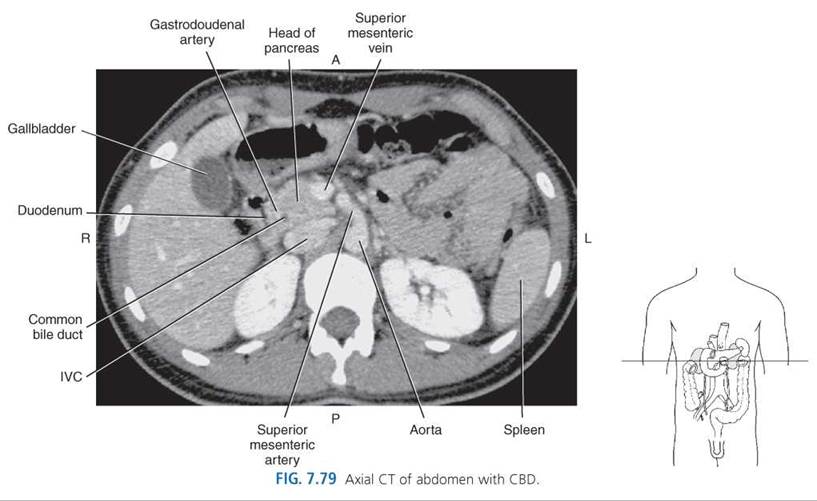

The CHD is located anterior to the portal vein and lateral to the hepatic artery in its caudal descent from the porta hepatis. As the CHD descends in the free border of the lesser omentum, it is joined from the right by the cystic duct to form the common bile duct (CBD). The CBD continues a caudal descent along with the hepatic artery and portal vein within the hepatoduodenal ligament (Fig. 7.68). It curves slightly to the right, away from the portal vein, then courses posterior and medial to the first part of the duodenum behind the head of the pancreas (Figs. 7.71, 7.72, and 7.75-7.79). The CBD follows a groove on the posterior surface of the pancreatic head, then pierces the medial wall of the second part of the duodenum along with the main pancreatic duct (duct of Wirsung) through the ampulla of Vater (Fig. 7.69). The ends of both ducts are surrounded by the circular muscle fibers of the sphincter of Oddi (Fig. 7.70).

PANCREAS